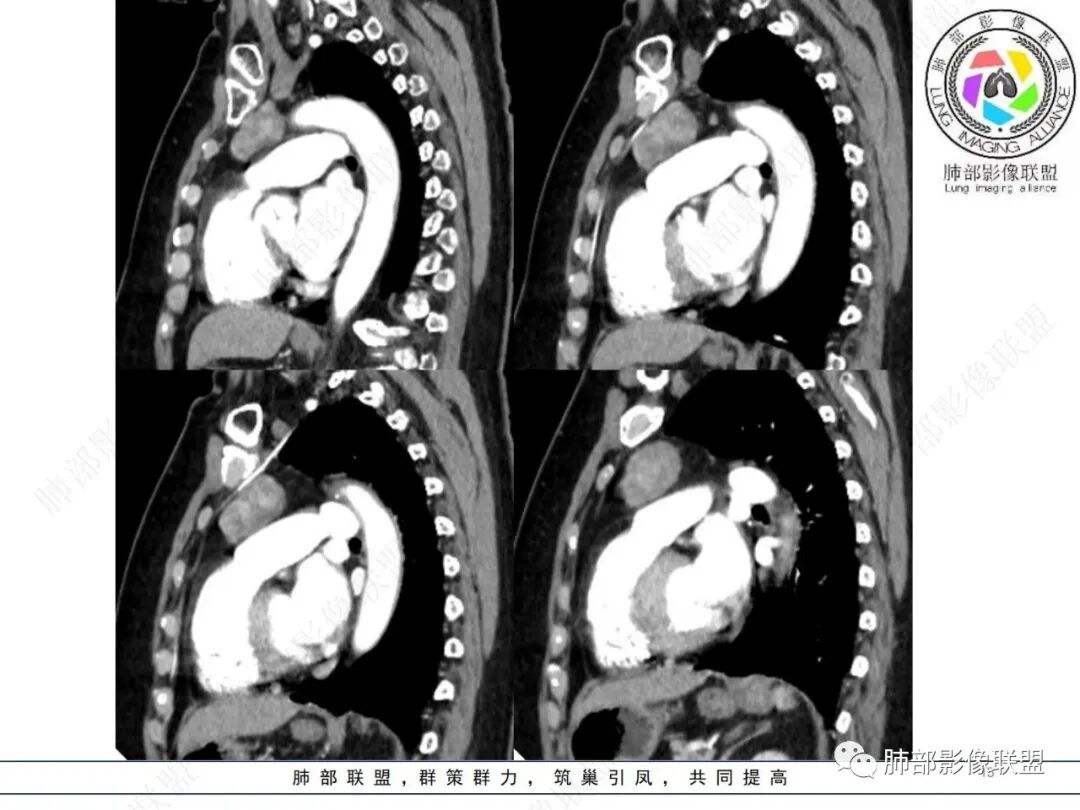

前上纵隔偏左侧实性病灶,边界清楚,边缘彭隆,浅分叶,内部密度均匀,未见钙化、脂肪密度,周围脂肪间隙清晰。

包膜完整,纤维分隔,结节感明显

平扫密度较均匀,增强渐进性不均匀强化,内见低密度纤维分隔。未见肿大淋巴结。未见胸腔积液。

肿块边界清楚,低密度纤维间隔,未见侵犯转移及增大淋巴结,多见于胸腺瘤AB型

—强化程度及强化方式不支持常见的血管瘤及巨淋巴结增生症(CD)。

—患者血压高,应当排除副节瘤可能。病灶未见坏死区,且发生于纵隔的嗜铬性副节瘤罕见。